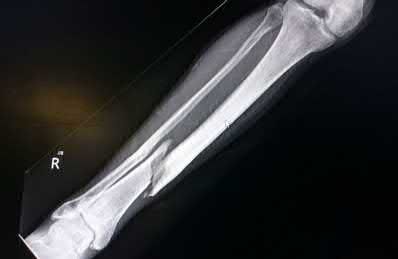

Question 3:

A 15-year-old boy presents with a permeative lytic lesion in the femoral diaphysis with aggressive periosteal reaction ('onion skinning'). Biopsy reveals uniform small round blue cells. Cytogenetic analysis of this tumor will most likely demonstrate which of the following translocations?

Correct Answer: t(11;22)

Explanation:

The clinical and radiographic description is classic for Ewing sarcoma. The characteristic cytogenetic abnormality is a balanced translocation t(11;22)(q24;q12), which fuses the EWS gene on chromosome 22 with the FLI1 gene on chromosome 11. This is seen in approximately 85-90% of Ewing sarcomas. t(9;22) is the Philadelphia chromosome (CML), t(X;18) is seen in synovial sarcoma, t(2;13) in alveolar rhabdomyosarcoma, and t(12;16) in myxoid liposarcoma.